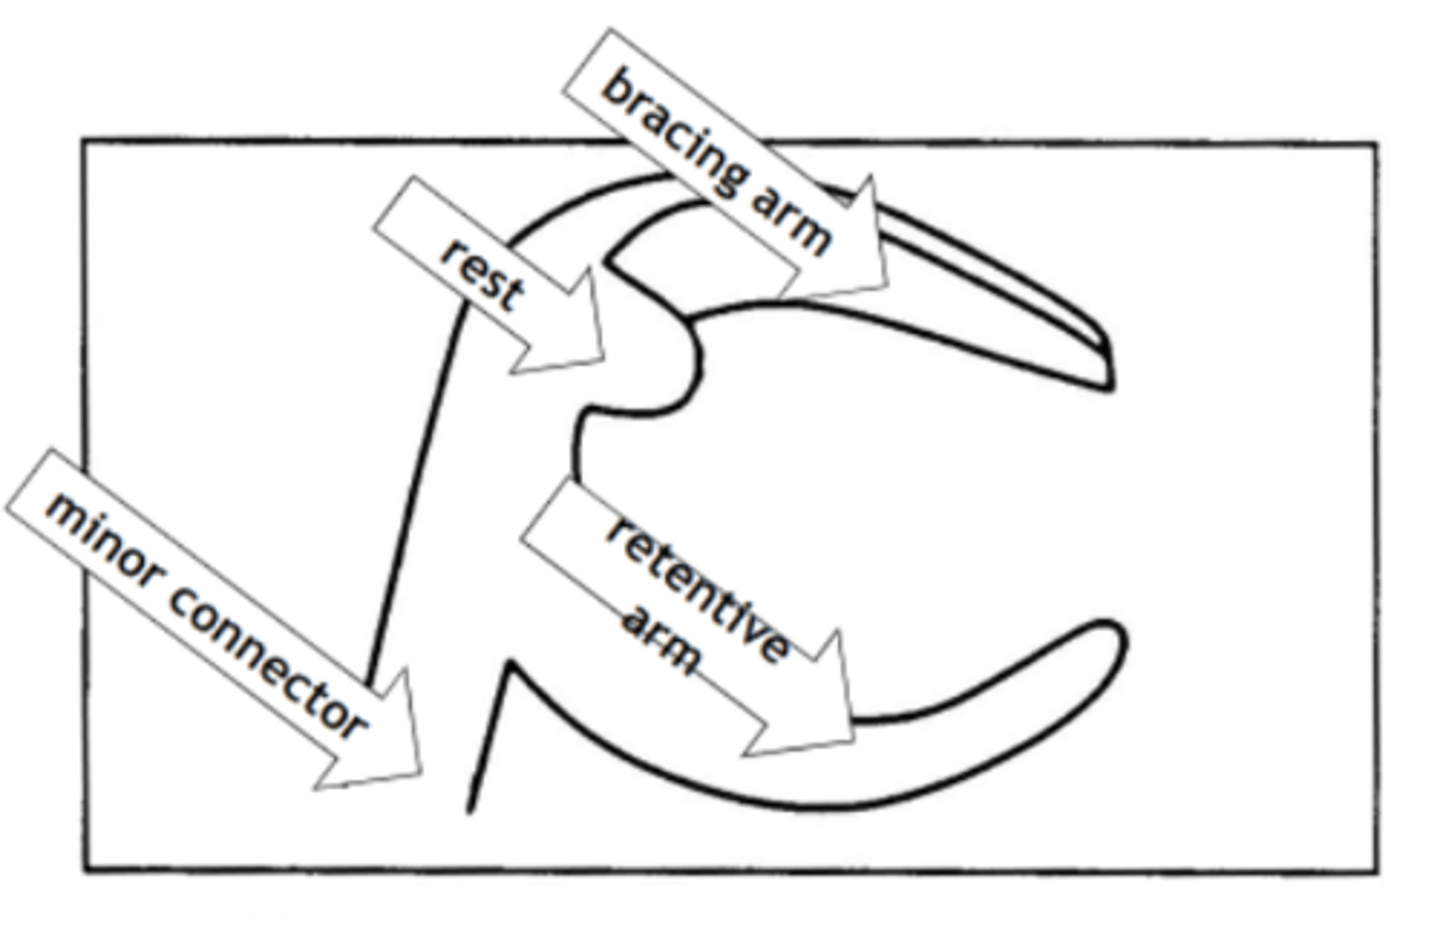

Clasp Assembly

An extra coronal direct retainer that engages an abutment tooth for retention, stability and support of the partial denture

minor connector.

Clasp assembly is made up of a bracing/stabilizing or reciprocating element, a rest, and retentive element, and is connected to the major connector via a ...

(The clasp engages a portion of the tooth surface and either enters an undercut for retention or remains entirely above the height of contour to act as a reciprocating or bracing element)

Minor connector

Connecting link between the major connector or base of the RPD and the other units of the prosthesis, such as the clasp assembly, indirect retainers or rests

Rest

RPD Components - Clasp Assembly Components:

Fits into a rest seat, which is a planned preparation on an abutment tooth. May be part of a clasp assembly (direct retainer), or may serve as an indirect retainer